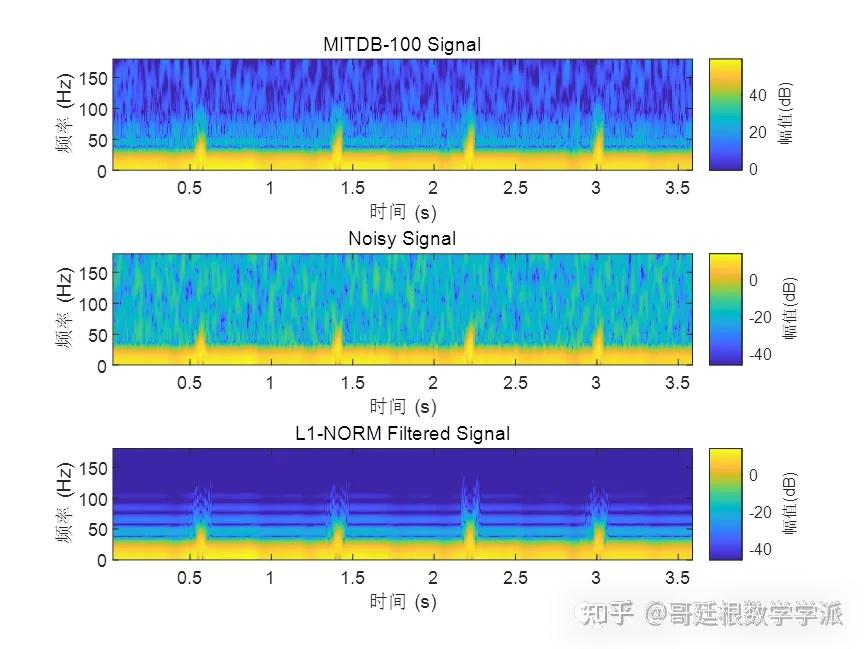

基于L1范数惩罚的稀疏正则化最小二乘心电信号降噪方法(Matlab R2021B)